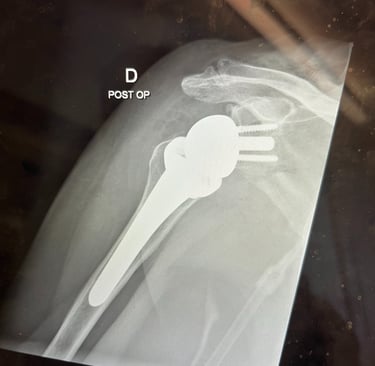

Mi occupo del trattamento delle principali patologie della spalla, con particolare esperienza nella protesica di spalla (anatomica e inversa). Tratto inoltre instabilità di spalla, lesioni della cuffia dei rotatori e traumatologia della spalla, con l’obiettivo di ripristinare la funzione articolare e ridurre il dolore attraverso tecniche chirurgiche moderne e personalizzate.